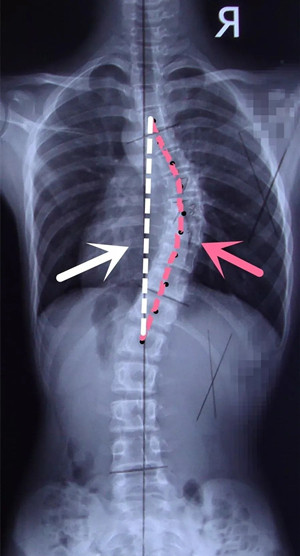

脊柱出現(xiàn)側(cè)彎后,軀干發(fā)生旋轉(zhuǎn)及扭曲變形,導(dǎo)致脊柱的縱向高度縮短,從而影響了患者的身高。度數(shù)嚴(yán)重的患者身高影響也嚴(yán)重,會(huì)使得身體比例出現(xiàn)異常。側(cè)彎對身高的影響與側(cè)彎的彎曲度數(shù)有直接的關(guān)系,國外的側(cè)彎治療工作者在患者的X片上進(jìn)行測量:找到要測量的彎弧上、下終椎,然后用一條弧線來串連上、下終椎之間各個(gè)椎體的中點(diǎn),最后再測量上、下終椎中點(diǎn)之間的直線距離,用弧線長度減去直線距離就得到了脊柱縮短的長度,這個(gè)代表了側(cè)彎對身高的影響數(shù)值。